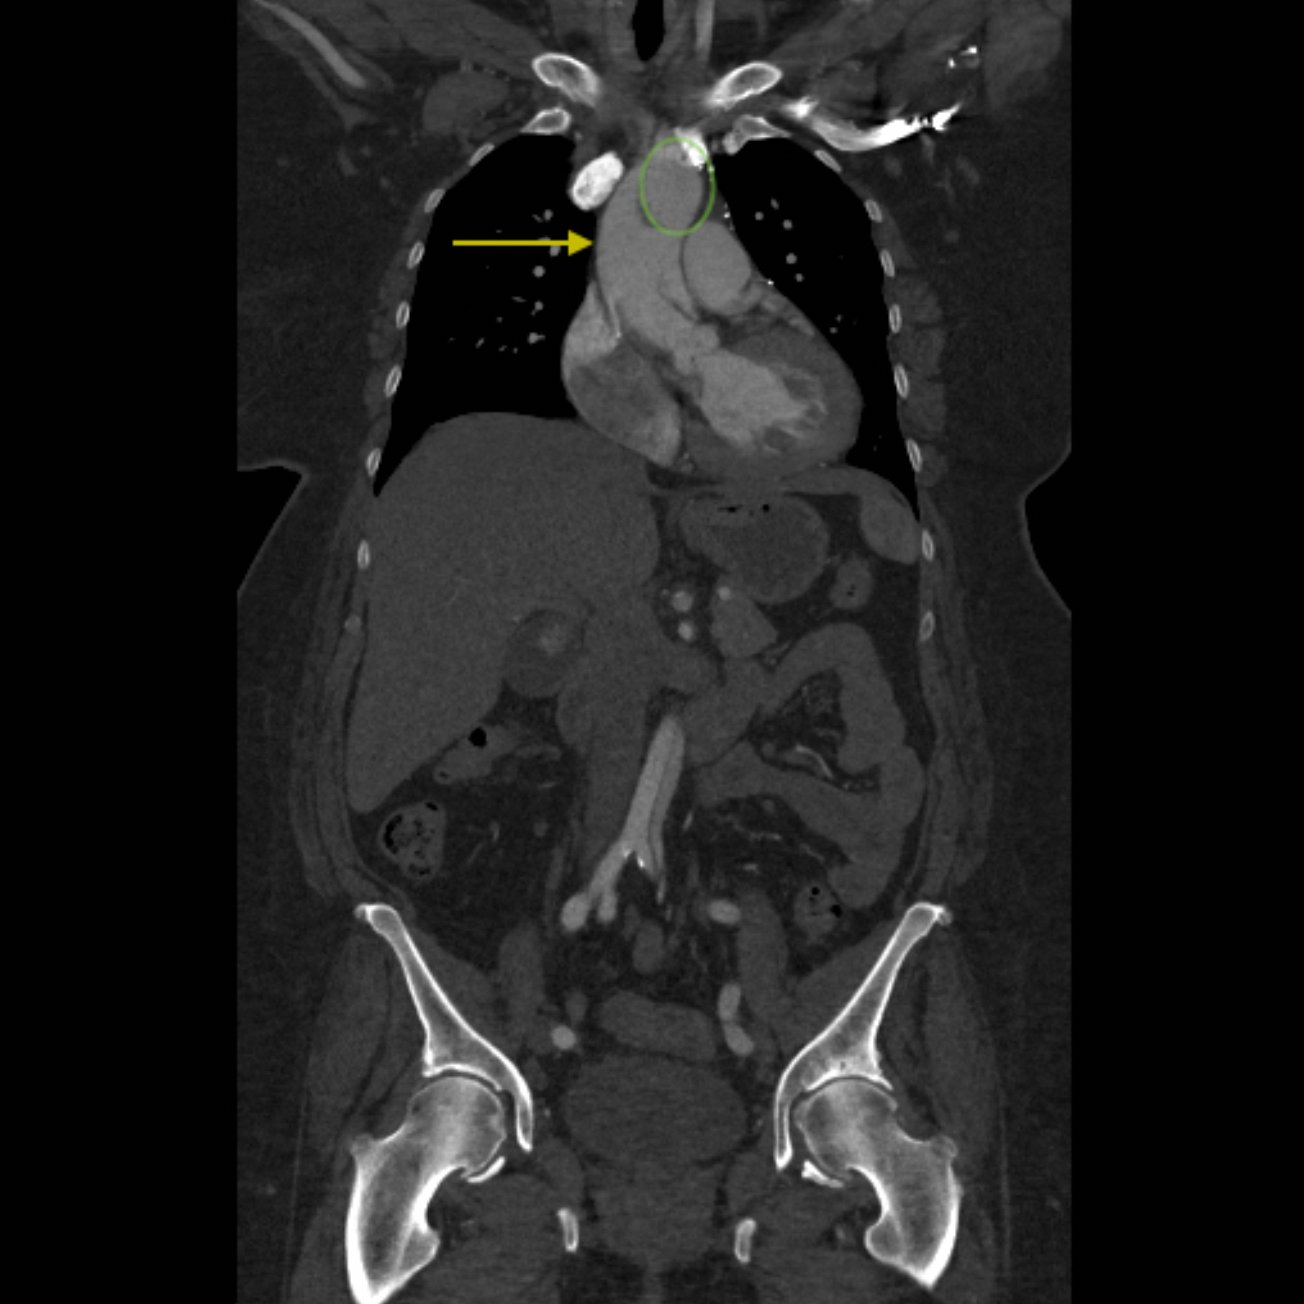

Because aortic dissection was suspected, the patient underwent urgent computed tomography (CT) angiogram of her chest, abdomen and pelvis that revealed her diagnosis.

The patient was found to have a Stanford type A dissection (see yellow arrow) with visible false lumen starting at aortic arch (see green circle). The dissection extended into the descending aorta (see blue circle) as shown by the false lumen (red highlighted area) visible on CT. The radiologist performed a reconstruction of the aorta, which showed that the left kidney was not being perfused, making the kidney not visible on the reconstruction.